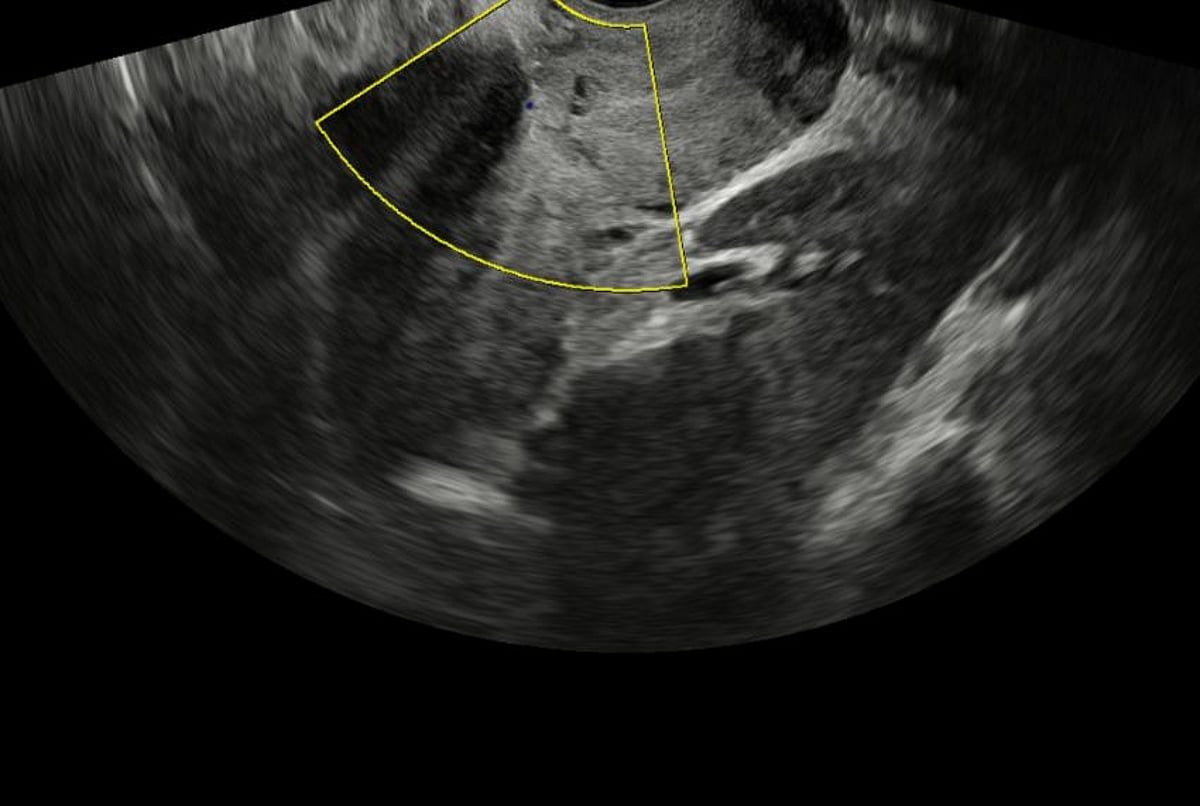

نجح مستشفى المانع العام بالدمام في إنقاذ حياة أم وجنينها بعد التعامل مع واحدة من أخطر حالات الحمل والولادة، والمتمثلة في المشيمة المنزاحة المصحوبة بالتصاق المشيمة، وهي حالة تُعد من أعلى حالات التوليد خطورة لما تحمله من احتمالية نزيف حاد قد يهدد حياة الأم.

وتعود تفاصيل الحالة إلى سيدة تبلغ من العمر 36 عامًا في الأسبوع الخامس والثلاثين من الحمل، حيث جرى تشخيص الحالة بدقة خلال فترة المتابعة الطبية، ووُضعت خطة علاجية مسبقة شاملة، تضمنت تجهيز فريق طبي متعدد التخصصات واختيار التوقيت والمكان الأنسب للتدخل، بما يضمن أعلى درجات السلامة للأم والجنين.